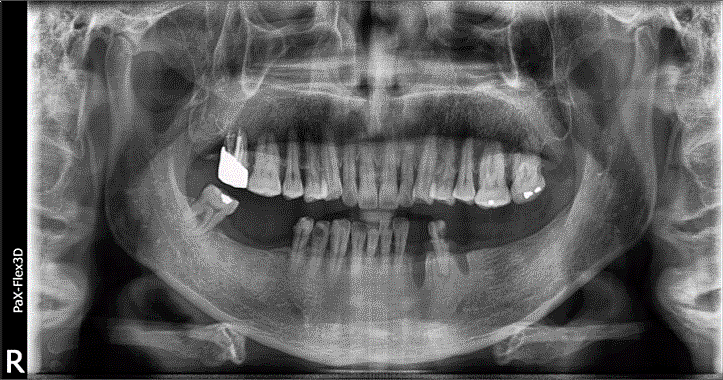

68세 남성

(전) 2021-11-05, (후) 2022-08-26

임플란트/크라운 시술 후

음식 섭취뿐만 아니라, 심미적인 개선으로

삶의 질이 높아진 환자분의 사례

잇몸뼈 부족으로 상악동거상술을 통한 뼈이식 진행한 환자분의 x-ray